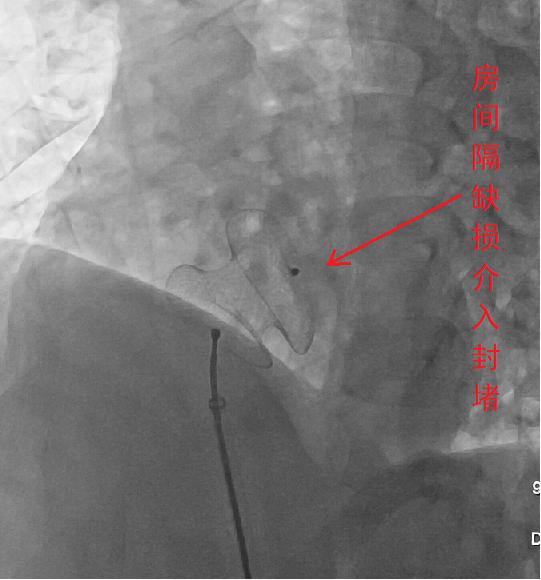

例如,采用介入插管行左心造影、右心造影并进行压力测定,能准确诊断房间隔缺损、室间隔缺损、肺动脉狭窄、法洛四联症、大动脉转位等先心病,成为确定心脏手术方案最有价值的评价手段。介入心脏瓣膜扩张成形术、冠状动脉狭窄扩张成形术、未闭动脉导管栓塞术等已在很大程度上替代了外科瓣膜分离术、冠脉搭桥术和动脉导管结扎术。冠脉粥样斑块旋切术、冠脉支架植入术已成为介入治疗冠心病的常用手段。通过皮下埋植永久性起搏器或实施心脏射频消融等介入技术治疗顽固性慢速型或快速型心律失常,已经成为经典甚至是首选治疗方案。

先天性心脏病也可介入治疗